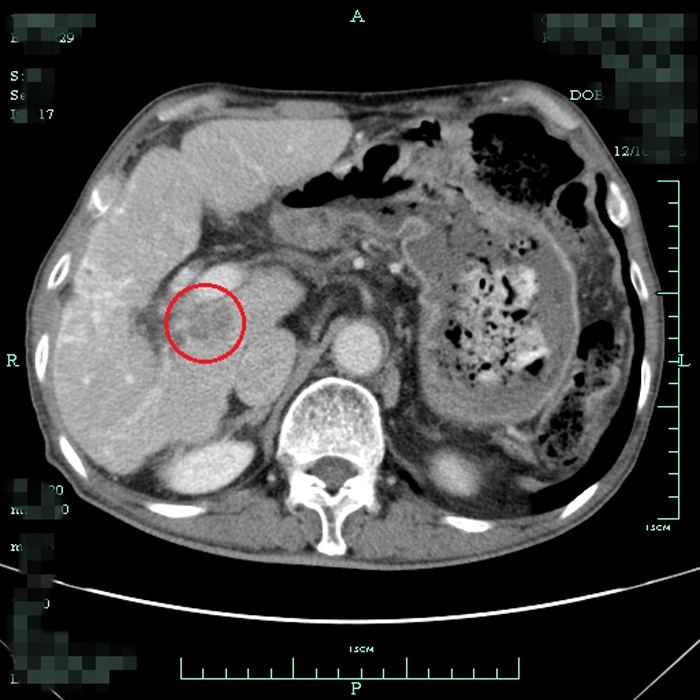

患者術(shù)前尾狀葉腫塊CT顯影

?? 據(jù)我院肝膽外科方劍醫(yī)生介紹,肝尾狀葉位于肝后下腔靜脈的前方,第一肝門的后方,三支肝靜脈的下方,亦即夾于三個(gè)肝門狹小空間之中,位置深,顯露困難,被認(rèn)為是肝臟手術(shù)的“最后禁區(qū)”。

?? 手術(shù)切除是尾狀葉腫瘤的主要治療方式。但由于其位置特殊,手術(shù)難度高,創(chuàng)傷大,風(fēng)險(xiǎn)極高。困擾他們一家的問題還不止這些,毛大爺原有肝硬化病史和肺癌手術(shù)史,高昂的手術(shù)費(fèi)用和較長的住院時(shí)間也成了加重家庭負(fù)擔(dān)的現(xiàn)實(shí)問題。有沒有一種治療效果與手術(shù)相近,而創(chuàng)傷更小、住院時(shí)間更短的治療方法呢?肝膽外科的醫(yī)生團(tuán)隊(duì)討論后決定采用射頻消融術(shù)來治療毛大爺?shù)奈矤钊~腫瘤。